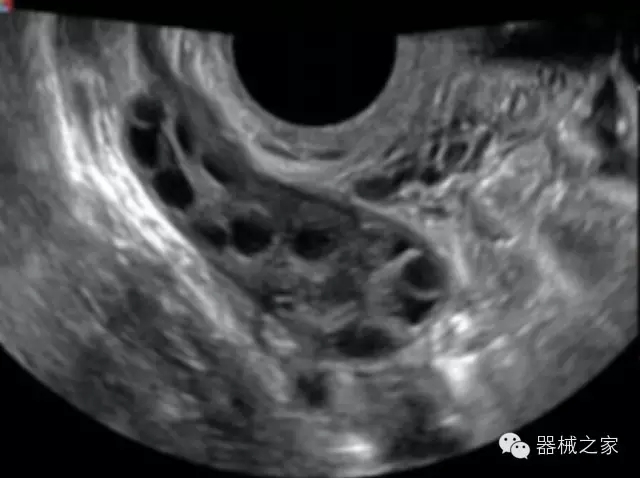

臨床圖片賞析

·智能微血流成像技術:智能微血流捕捉技術可以提取出隱藏在背景噪聲中的弱血流信號,大大提高低速血流的敏感性;

·實時的彈性成像技術:提高了小器管(乳腺,甲狀腺、淺表軟組織腫瘤等)疾病鑒別診斷;

·高效3D/4D成像技術:高速的4D幀頻,豐富的3D成像模式,智能斷層切片功能;

·獨有的大角度及實時溫控技術,能同一切面顯示宮頸及宮體,有效減低了患者的痛苦,及保護粘膜保證了醫(yī)療安全;